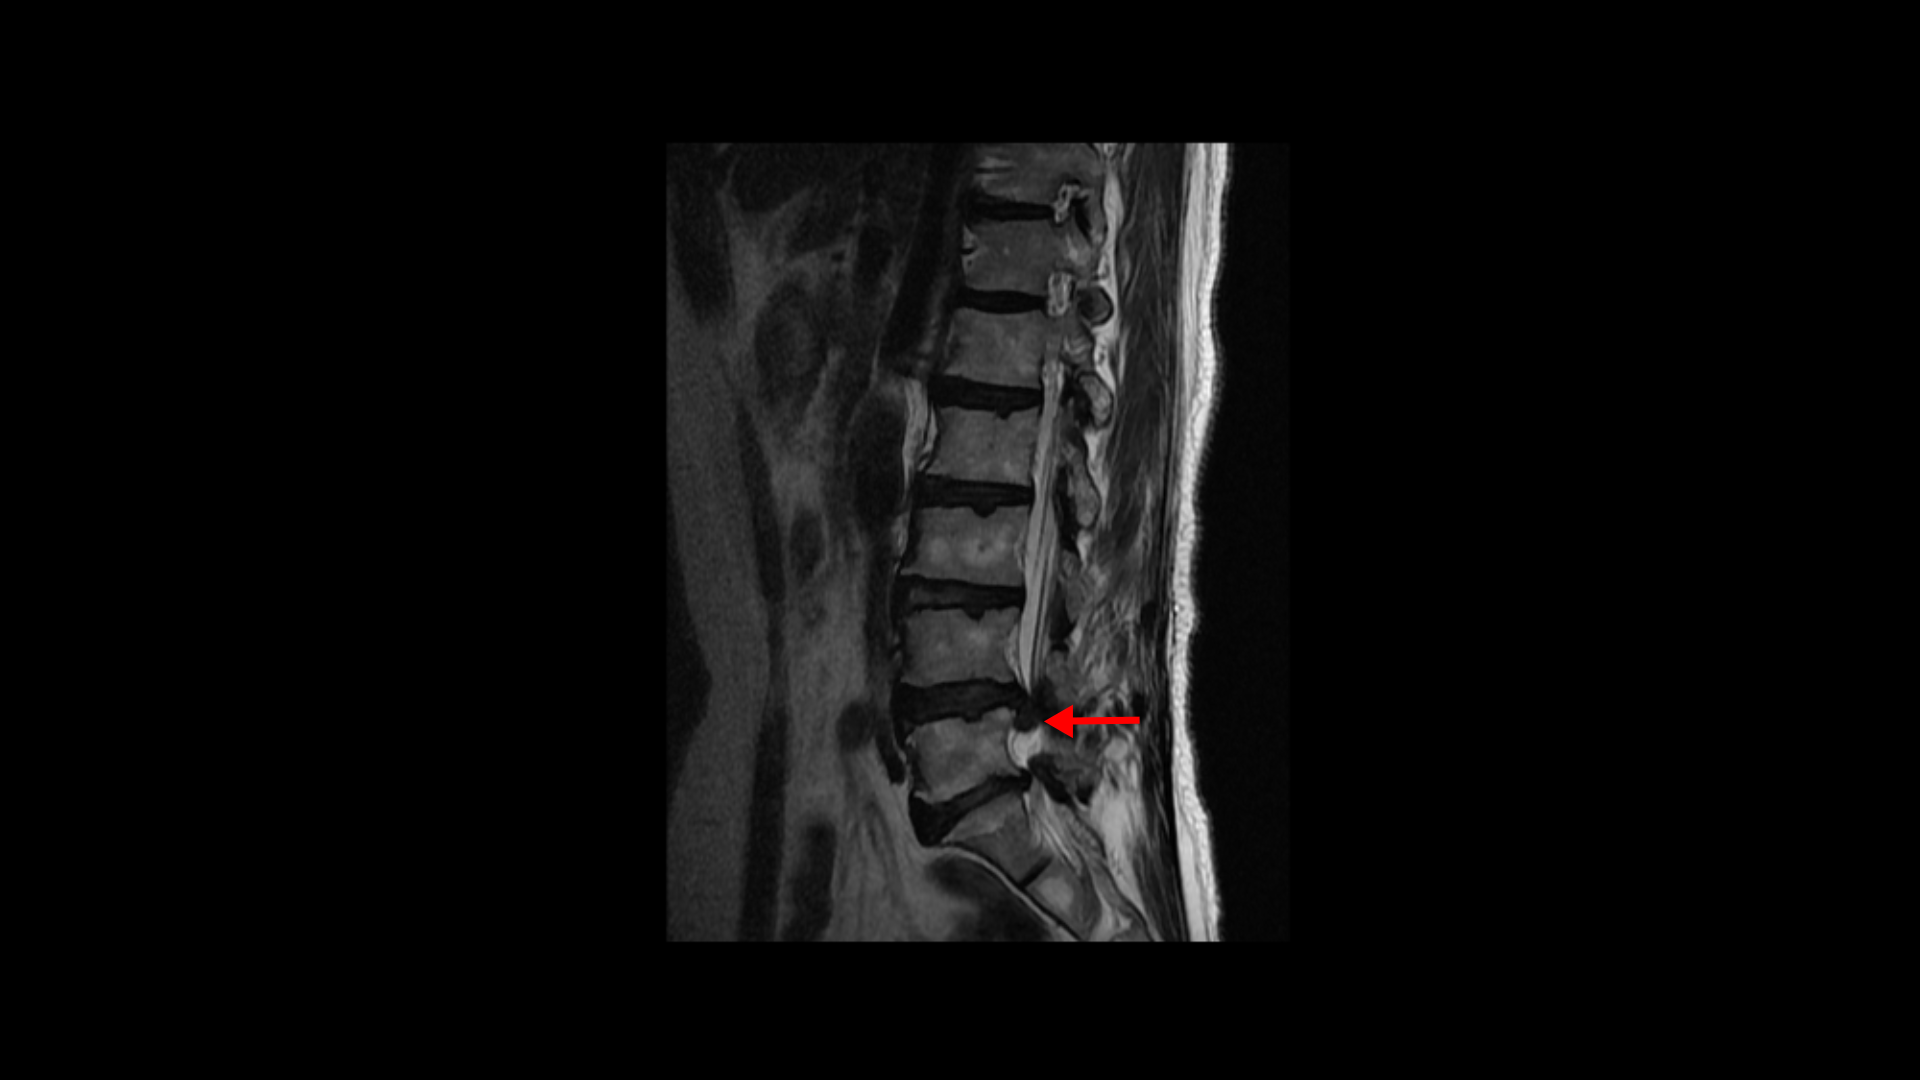

이분은 약 4달 전에 디스크가 갑자기 파열됩니다. MRI를 보면 4번 5번 디스크가 터져서 밀려나온 수핵이 아래로 흘러내려 있습니다.

이 파열된 디스크로 인해 극심한 엉치 통증과 다리의 방사통이 발생합니다.